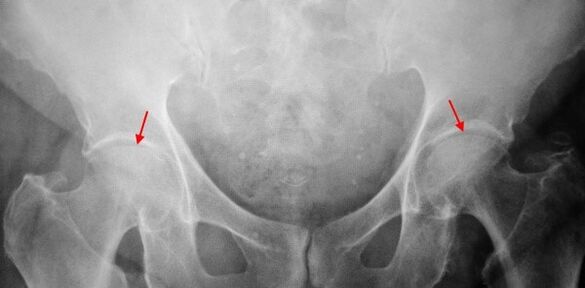

On the patient's X rays, which suffers from coxarthritis of the 1st degree, mild changes are determined: a moderate uneven narrowing of the joint column as well as bone growth around the outer or inner edge of the acetabulum without changes from the head and neck of the thigh.

In x radiation images for the coxarthritis of the 2nd degree, a significant narrowing of the common gap (more than half of the normal height) is determined.The thigh head is slightly moved up, deformed and increased, and its contours become uneven.Bone growth with this degree of coxarthrosis occurs not only on the inside, but also on the outer edge of the acetabulum and goes outside the cartilage.

In the case of X -rays for the coxarthritis of the 3rd degree, a sharp narrowing of the joint column, a pronounced expansion of the thigh head and several bone growth is demonstrated.

The diagnosis of coxarthrosis is based on clinical signs and data of additional studies that are radiography.In many cases, X rays enable not only the degree of coxarthrosis, but also the cause of its appearance.For example, the scenes and the flattening of the acetabulum indicate an increase in the neck diaphysical angle, and the form of the proximal part of the femur are indicated that coksart rose is a consequence of the disease or the youthful epiphysissis of pertes.In the case of X -rays of patients with coxarthrosis, changes can also be determined that indicate injuries.